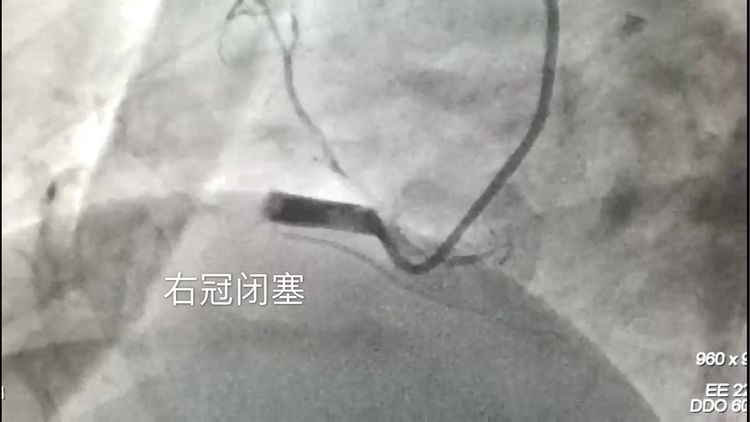

急诊冠脉造影,按照常规,先做左边血管,再做右边血管,可是情势紧急,主任根据病人症状,心电图,判断右冠是罪犯血管,先开始右侧血管造影,果然,右冠闭塞。